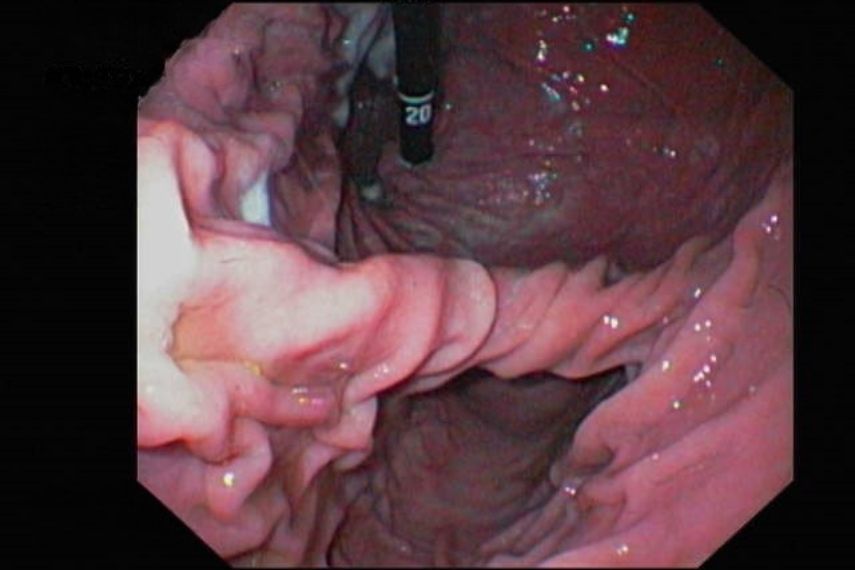

Als Gastroduodenoskopie bezeichnet man die endoskopische Untersuchung des Magen-Darm-Trakts, angefangen von der Maulhöhle über die Speiseröhre bis in den Magen und den Anfangsbereich des Zwölffingerdarms. Indikationen für eine Magen-Darm-Spiegelung sind chronisches Erbrechen, längere Inappetenz, vermehrter Speichelfluss, saures Aufstoßen, Regurgitieren, Gewichtsverlust, Meläna, Fremdkörperverdacht und viele mehr. Veränderungen der Magenschleimhaut wie Geschwüre, Blutungen, Polypen oder Tumore können so festgestellt und Gewebeproben (Biopsien) davon entnommen werden. Auch eine Fremdkörperentfernung kann in einigen Fällen mittels Gastroskop durchgeführt werden.

Gastroskopie – endoskopische Aufnahme des Magens

Endoskopie Magen